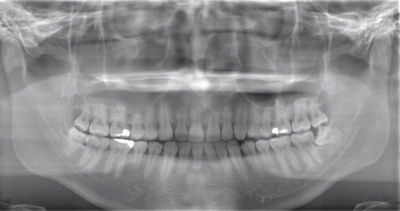

CASE 4

| 年齢・性別 | 30代・男性 |

| 主訴 | 左上親知らず抜きたい |

| 抜歯期間 | 15分 |

| 抜歯費用 | 約2,000円(保険内) 別途CT撮影で3,000円 |

| 抜歯内容 | 左上の親知らず抜歯 |